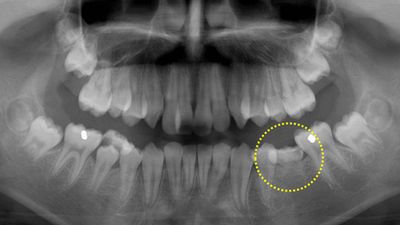

12歳の男の子、前歯がガタガタで出っ歯が気になるので矯正相談に来られました。レントゲン撮影したところ、下顎の第二小臼歯(黄色い丸で囲った部分)が先天的に欠損していて、乳歯がそのまま残っていることが判明しました。両隣りの永久歯に比べて高さが一段低くなっていて、咬み合せに問題があります。このような乳歯はいずれ駄目になって抜歯することになります。今回は、非抜歯矯正を希望されたのでまずはこのままの状態で矯正治療をスタートしました。大学に進学した後に乳歯を抜歯しての再治療を検討するとのことです。